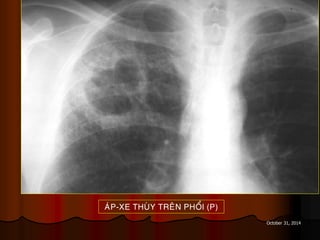

AÙP-XE THUØY TREÂN PHOÅI (P)

October 31, 2014 AÙP-XETHUØY TREÂN PHOÅI (P)